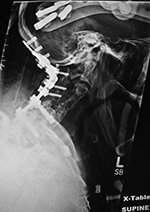

Elderly woman with diskitis at C4-5 and adjacent bony destruction by osteomyelitis at C4 and C5. Initial cervical fusion failed. A corpectomy cage was placed at C4-5 with posterior spinal fusion from the occiput to T2. A crosslink is at C6. |